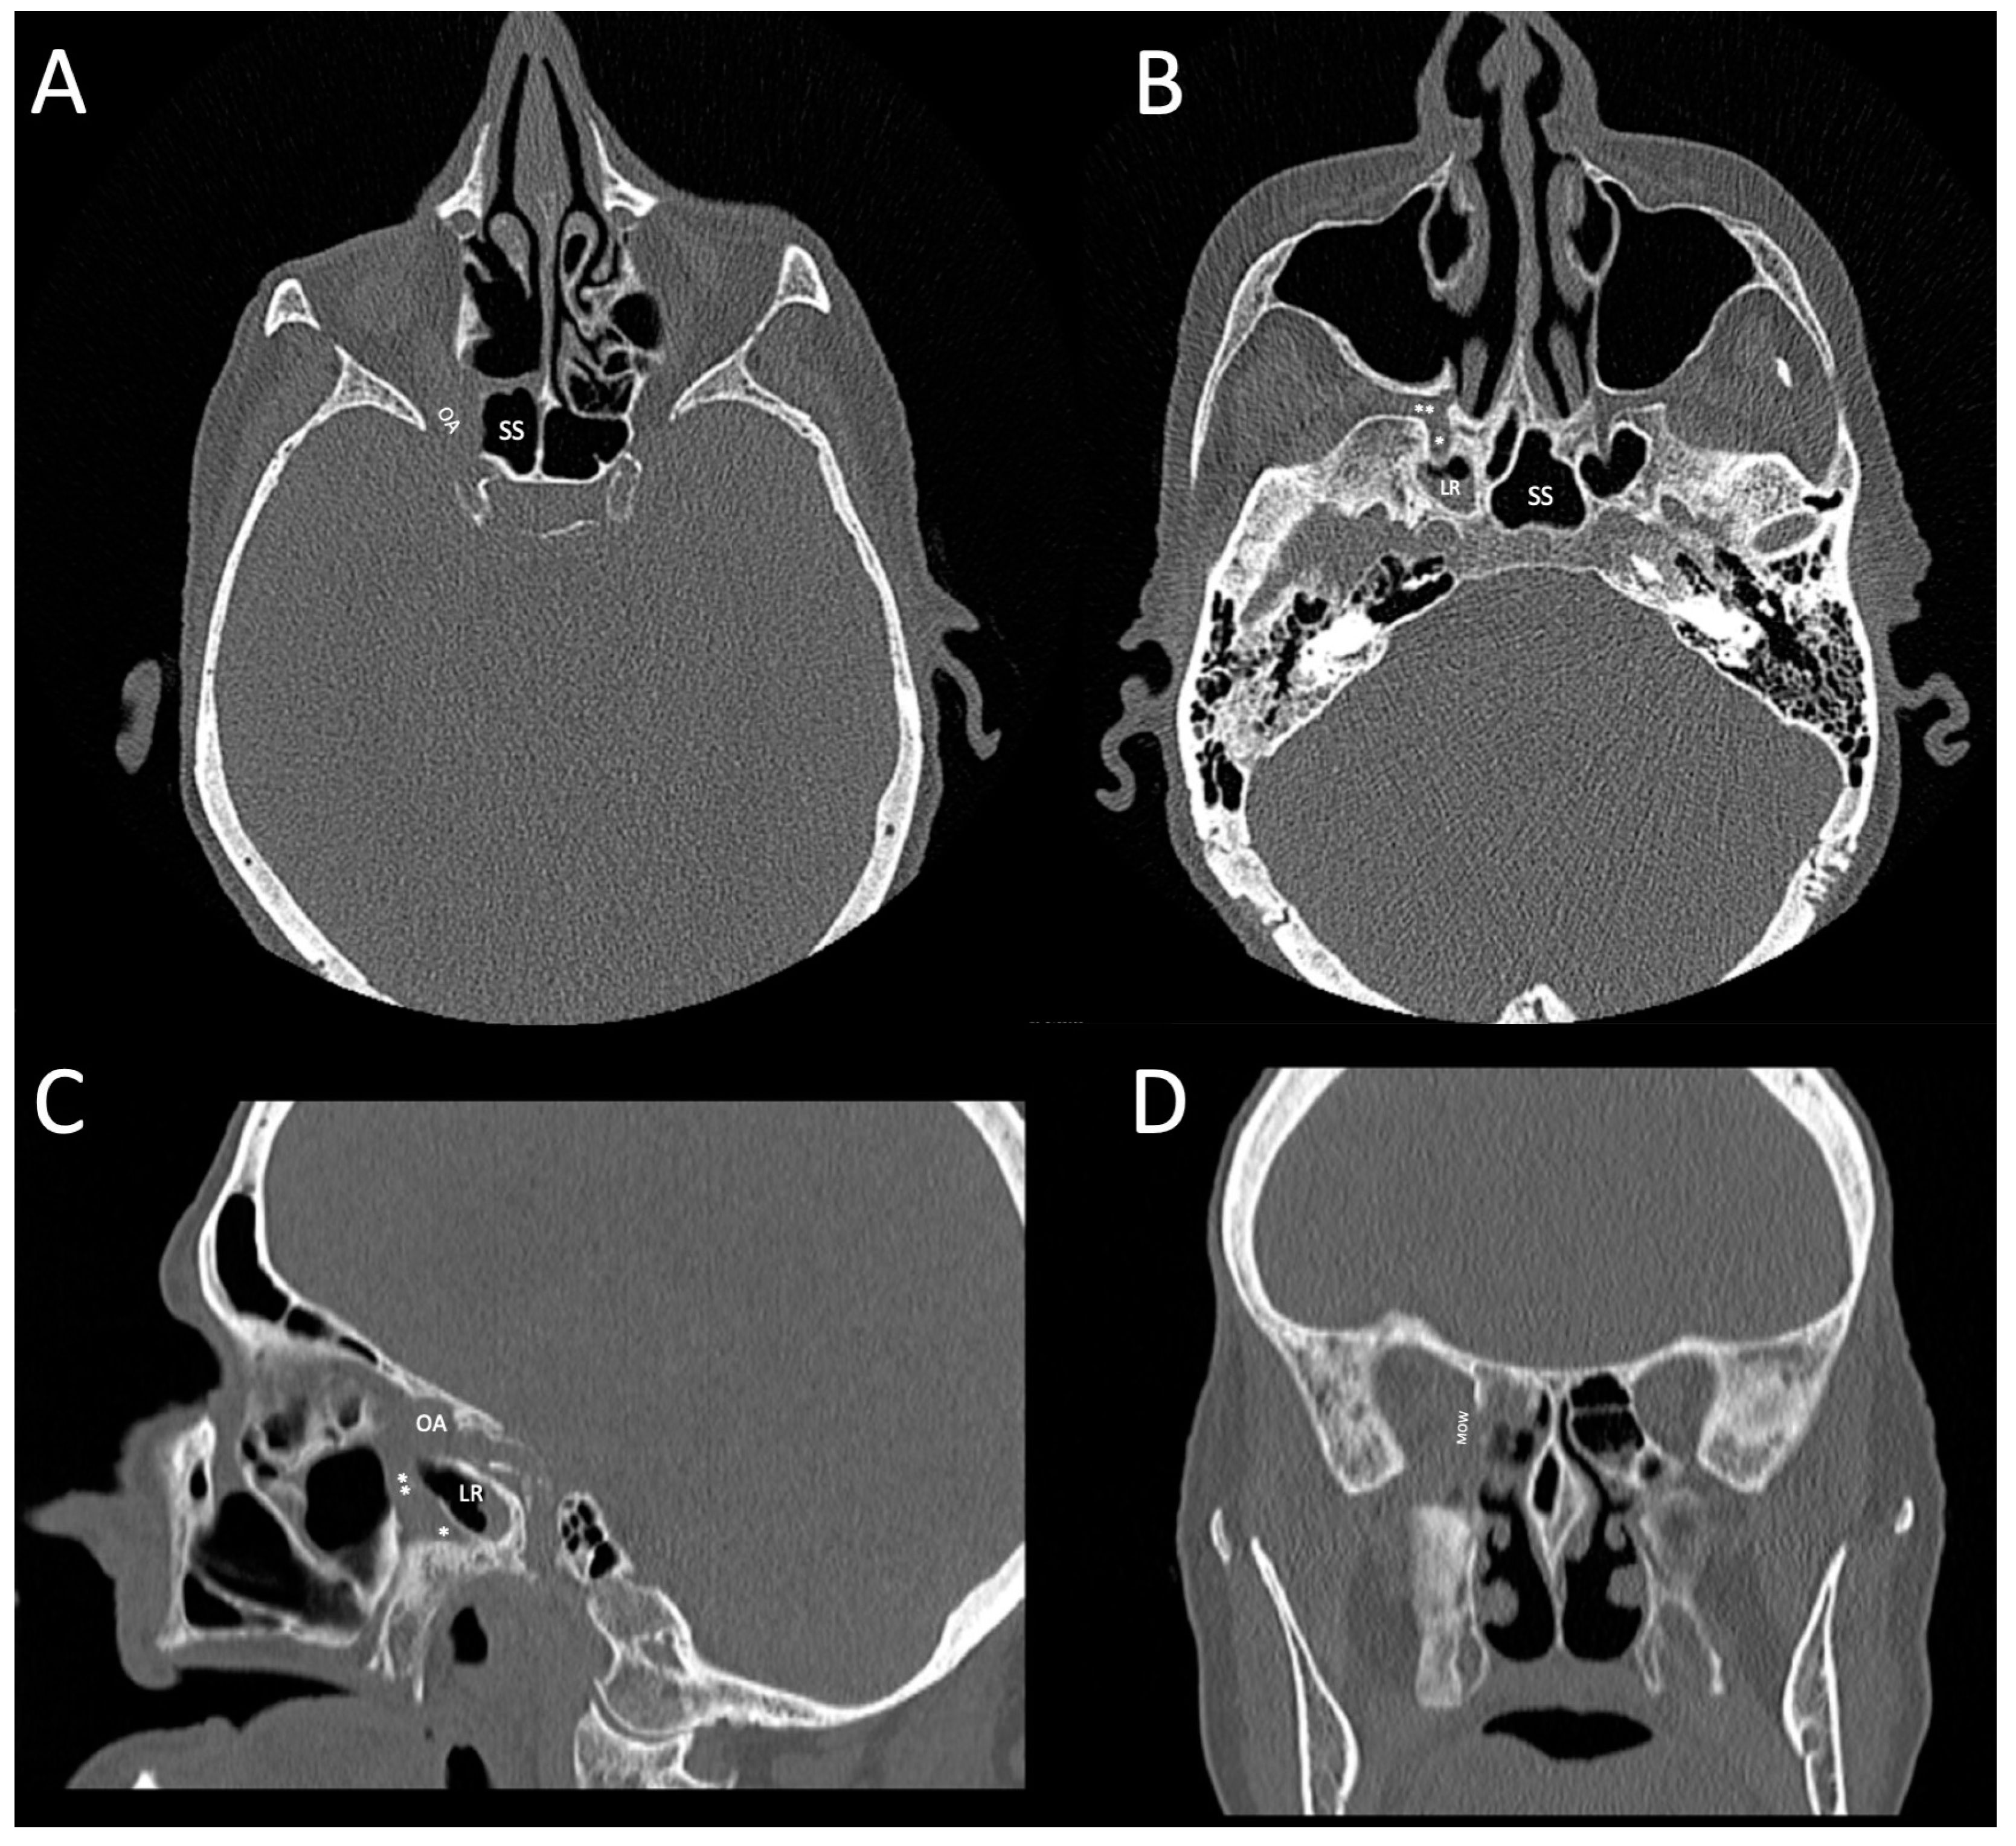

2.1. Initial Presentation and Treatment

2.2. Revisional Treatment